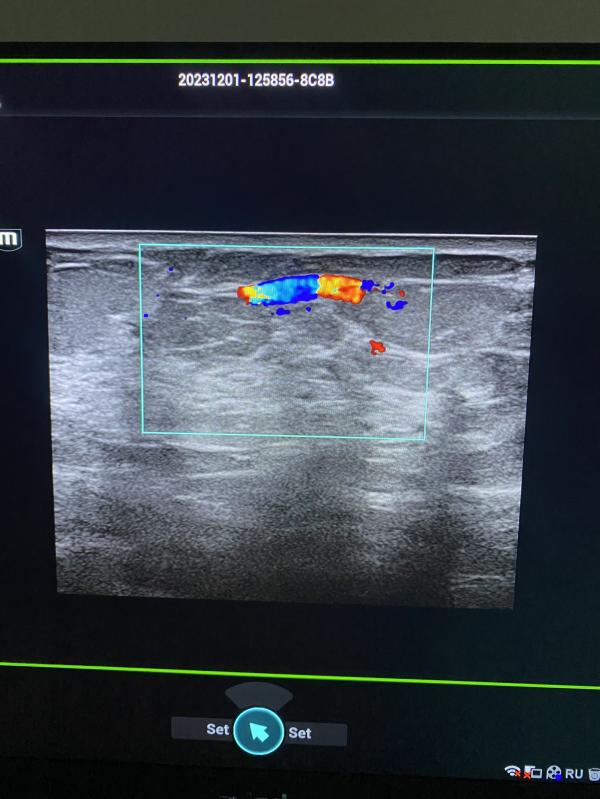

Нужно ли делать УЗИ молочных желез, если обнаружили патологию? Консультация маммолога и дообследование

post image 1

Выявлены патологические участки в правой молочной железы. Пациентка отправлена на дообследование к маммологу.